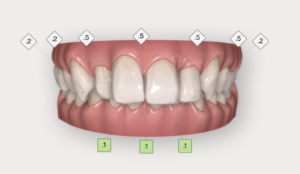

最初の状態がこちらです。

前歯には3本被せ物がしてある状態でした。

歯頚ラインとは前歯の歯茎の並びと言い換えるとわかりやすいかもしれません。

左右でこのラインが不揃いなのがわかります。

今回は上記の「2」の矯正治療のインビザライン(インビザラインGoという部分矯正プラン)で前歯のラインを合わせてから被せ物を行う計画を立てました。

前歯の被せ物をいったん、仮歯に置き換えてから

歯頚ラインが整ってきましたら、ポリリン酸ホワイトニングで色を明るくして

そして、最後にオールセラミックで仕上げを行います。

このように、とても調和の取れたバランスの良い前歯になりました。

前歯の被せ物を交換するだけではこの自然感は得られません。